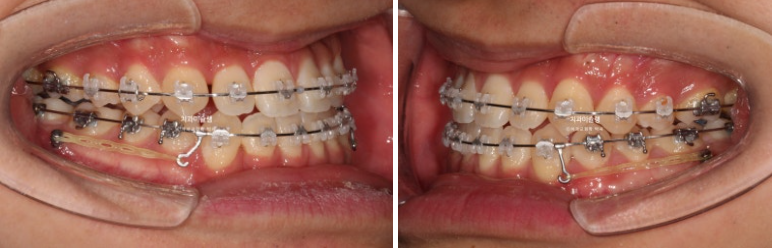

24.06

치료시작 1년째 모습입니다.

이때까지는 월 1회 꾸준히 내원했으나 이 시점 군입대를 하게 되셨습니다.

입대 후 3-4개월에 한번씩 내원하면서 치료를 이어갔습니다.